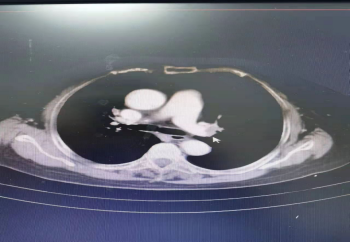

第二,开展新技术新业务,填补彭水县的医疗领域的空白。与彭水血管外科团队通力合作,先后开展了主动脉夹层腔内隔绝术,肺动脉造影吸栓术各1例,手术效果良好,患者均已康复出院,回访患者恢复良好。

典型病例资料1: